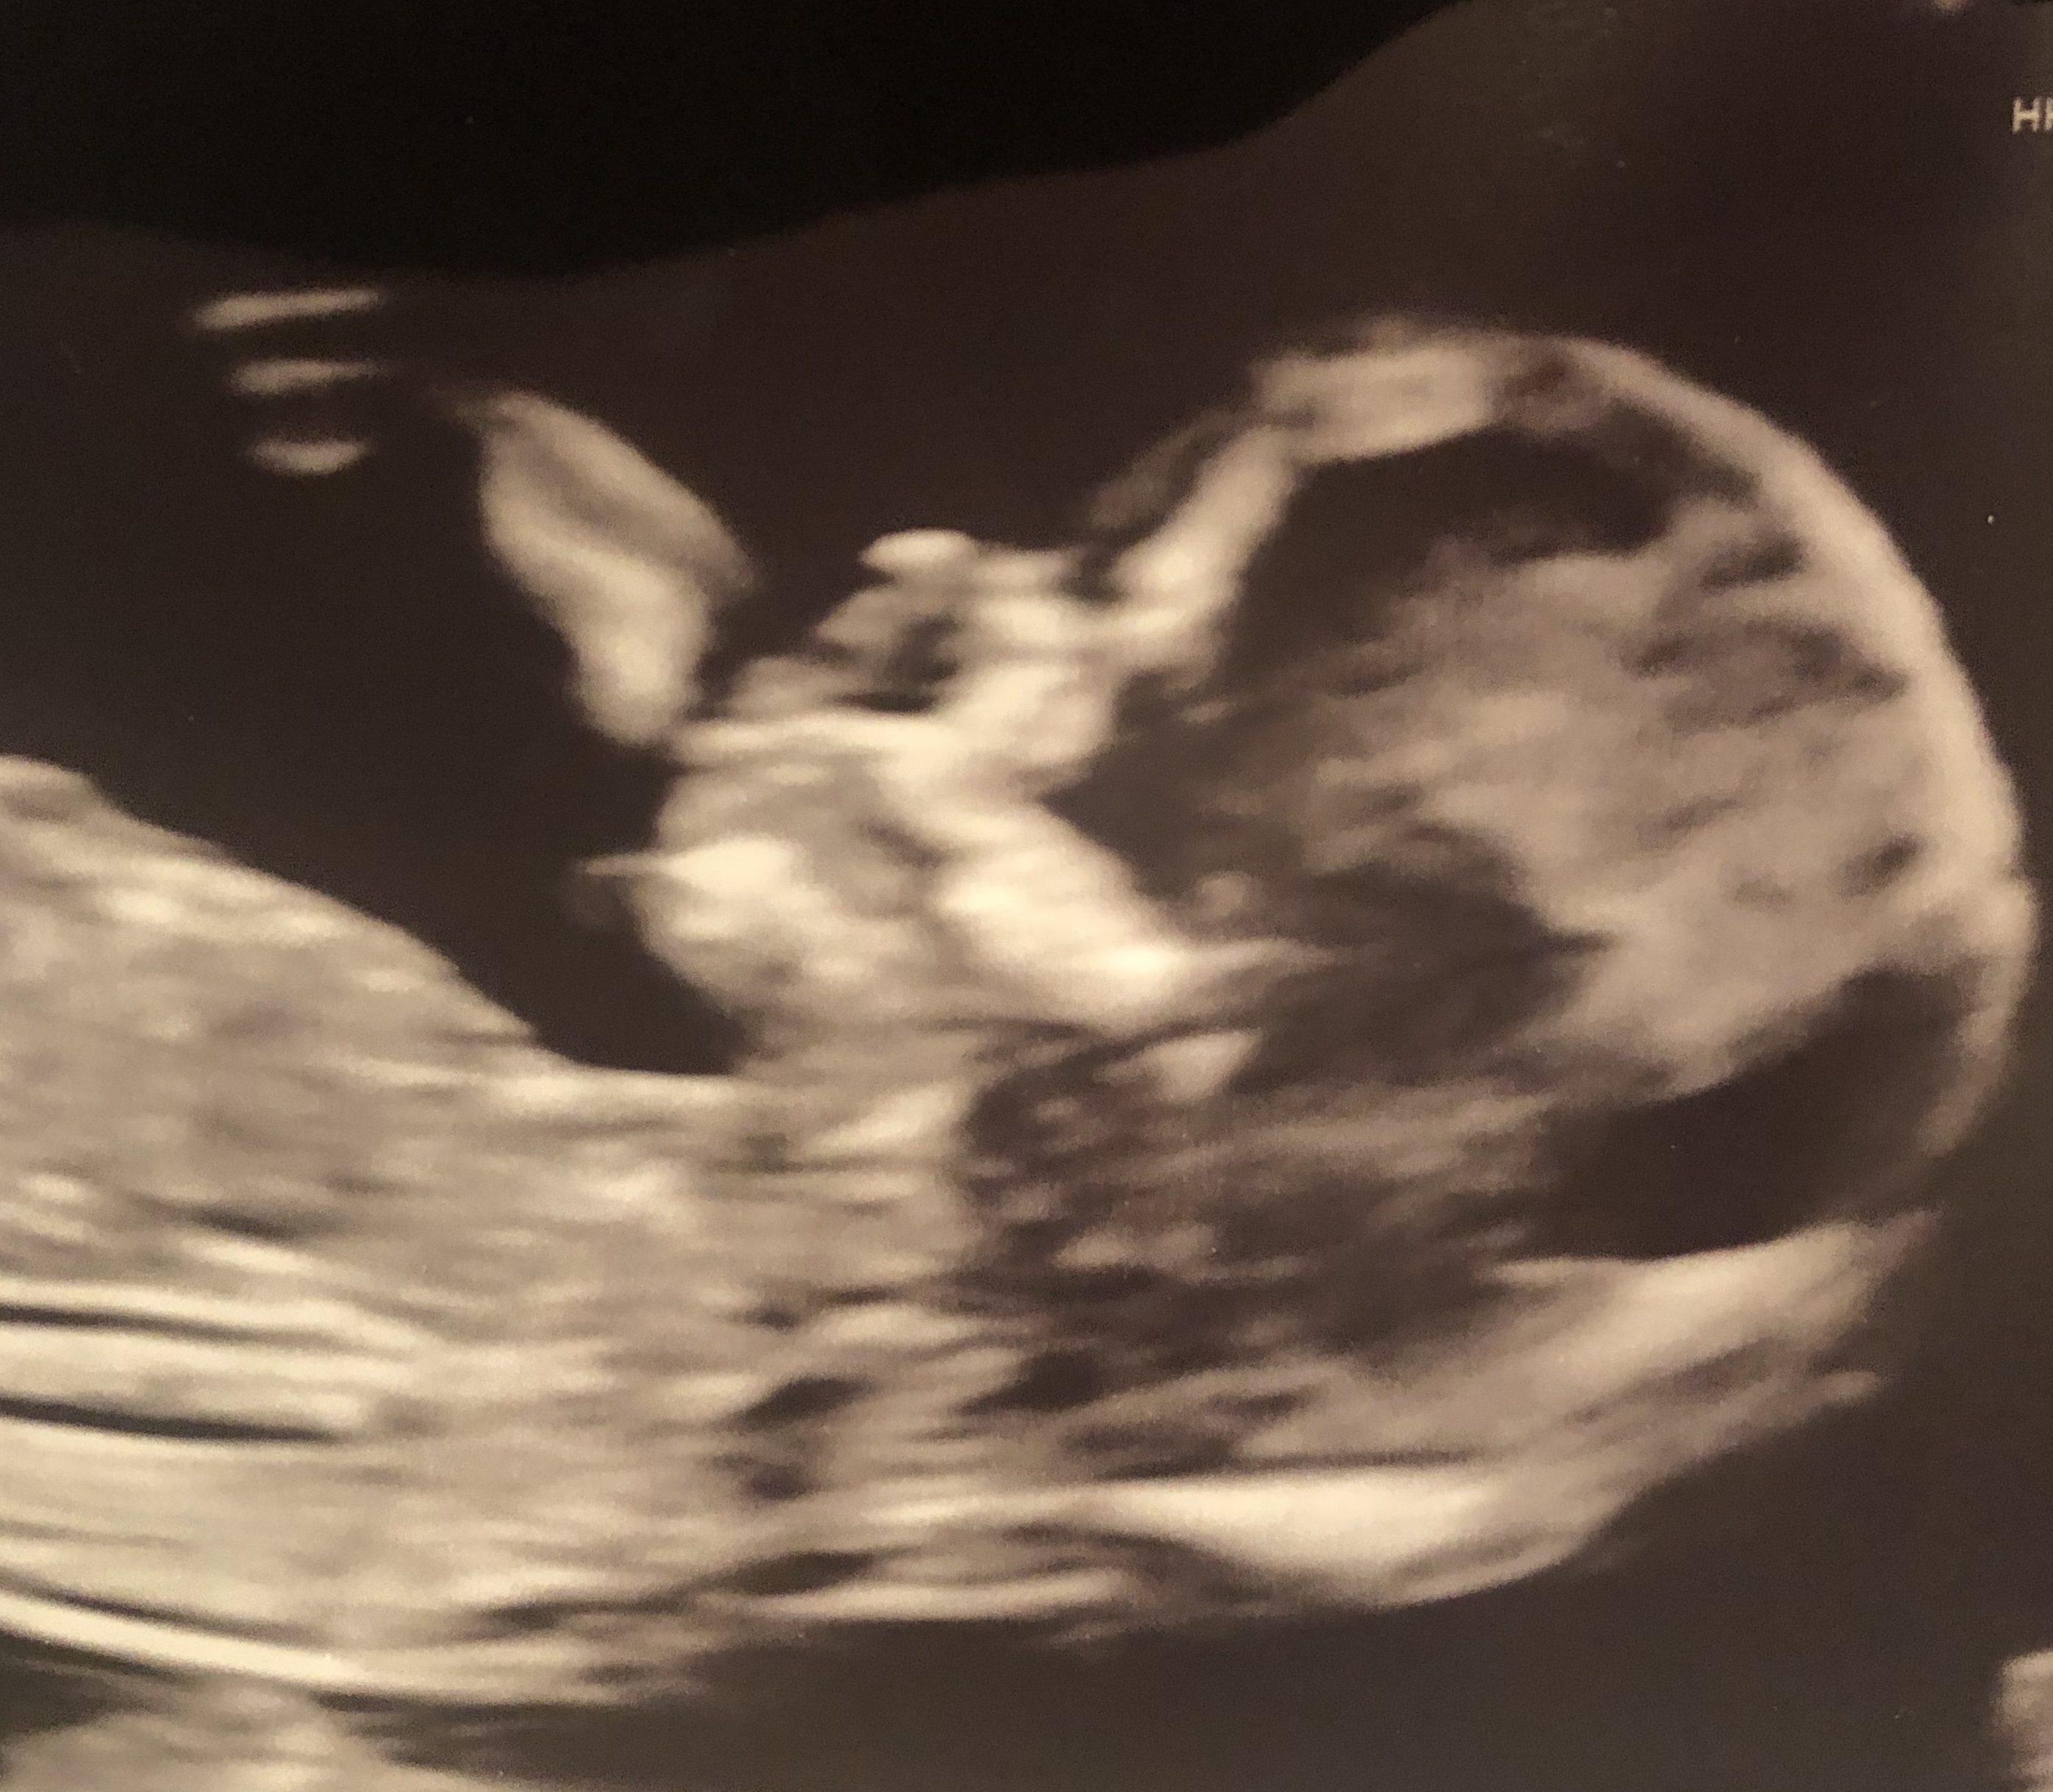

Skull theory 12 weeks

No Nub visible on my photos. Any guesses based on skull theory?